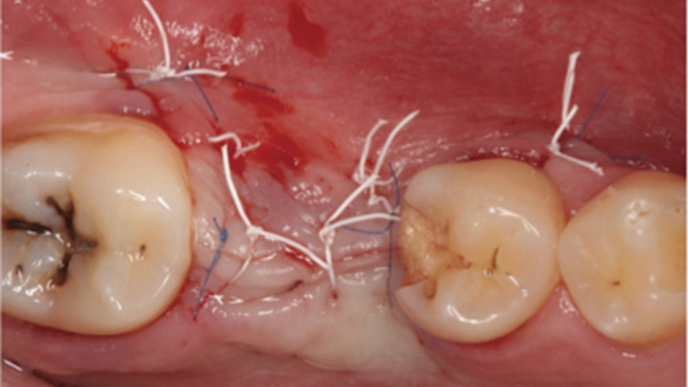

Clinical case: # 46 implant placement & GBR using i-Gen membrane for significant vertical resorption & mixed bone defect

AnyRidge, mandibular posterior, i-Gen, resorption, bone defect, bone regeneration, space management, #46, GBR, Dr. Iulian Filipov

AnyRidge implant system, i-Gen

“AnyRidge KnifeThread achieves excellent stability in regenerated bone & even in only 3mm bone height!”